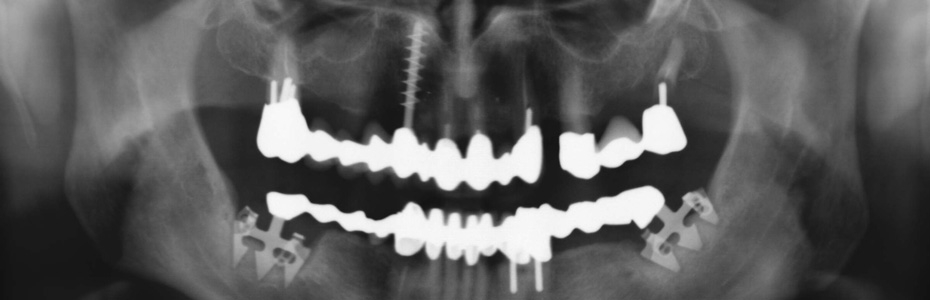

Implantologische Misserfolge

Ein Misserfolg muss nicht immer ein Implantatverlust sein. Auch eine Abweichung von dem mit dem Patienten geplanten und dem erzielbaren Ergebnis kann als Misserfolg verstanden werden.

Vom Misserfolg zur erfolgreichen Behandlung

Unkenntnis oder Versäumnisse

Implantologische Misserfolge können auf Unkenntnis von Begleitumständen und einer ungünstigen Abfolge von Ereignissen oder Versäumnissen beruhen.

Wir zeigen Ihnen an dieser Stelle Patientenfälle, die vorbehandelt in die Praxisklinik für dentale Implantologie gekommen sind und für die wir im Rahmen einer Weiterbehandlung eine Lösung gefunden haben. In vielen Fällen haben wir festgestellt, dass die Misserfolge vorhersehbar und vermeidbar gewesen wären.